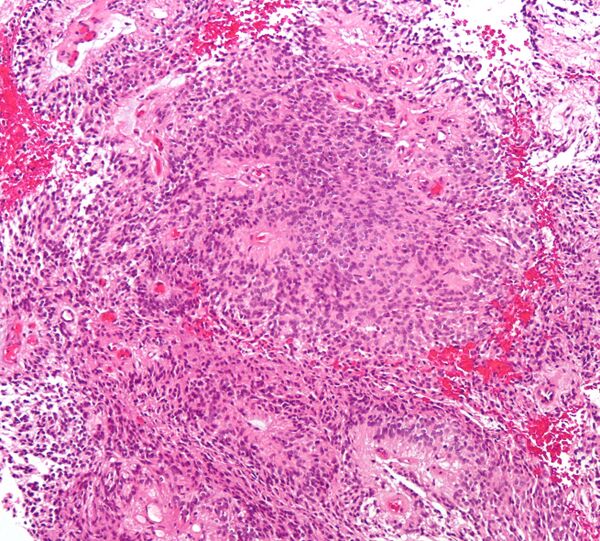

Микропрепарат истинной эпендимомы. На изображении видны как истинные, так и псевдорозетки

1. Основным гистологическим типом является истинная эпендимома , для которой типично наличие периваскулярных и истинных «розеток». Периваскулярные «розетки» («псевдорозетки», «лучистая корона») состоят из клеток новообразования, которые располагаются вокруг кровеносных сосудов. В истинных «розетках» опухолевые клетки находятся вокруг каналов, которые выстланы эпендимарными клетками.